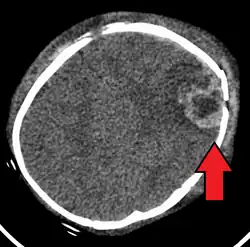

| An intraparenchymal bleed with overlying skull fracture from shaken baby syndrome | |

Diagnosis can be difficult as symptoms may be nonspecific.[1] Symptoms may include altered mental status, trouble breathing, and vomiting.[7] As a result, about 31% of true SBS cases may go unnoticed initially. However, imaging can provide valuable information about a potential SBS diagnosis.[58] Imaging must be performed within at least 24 hours of the suspected injury to detect brain edema characteristic of SBS.[59] A CT scan of the head is typically recommended if a concern is present.[1] If there are concerning findings, a brain MRI is also recommended, which can further reveal parenchymal injuries and hemorrhages.[58] It is unclear how useful subdural haematoma, retinal hemorrhages, and encephalopathy are alone at making the diagnosis.[11]